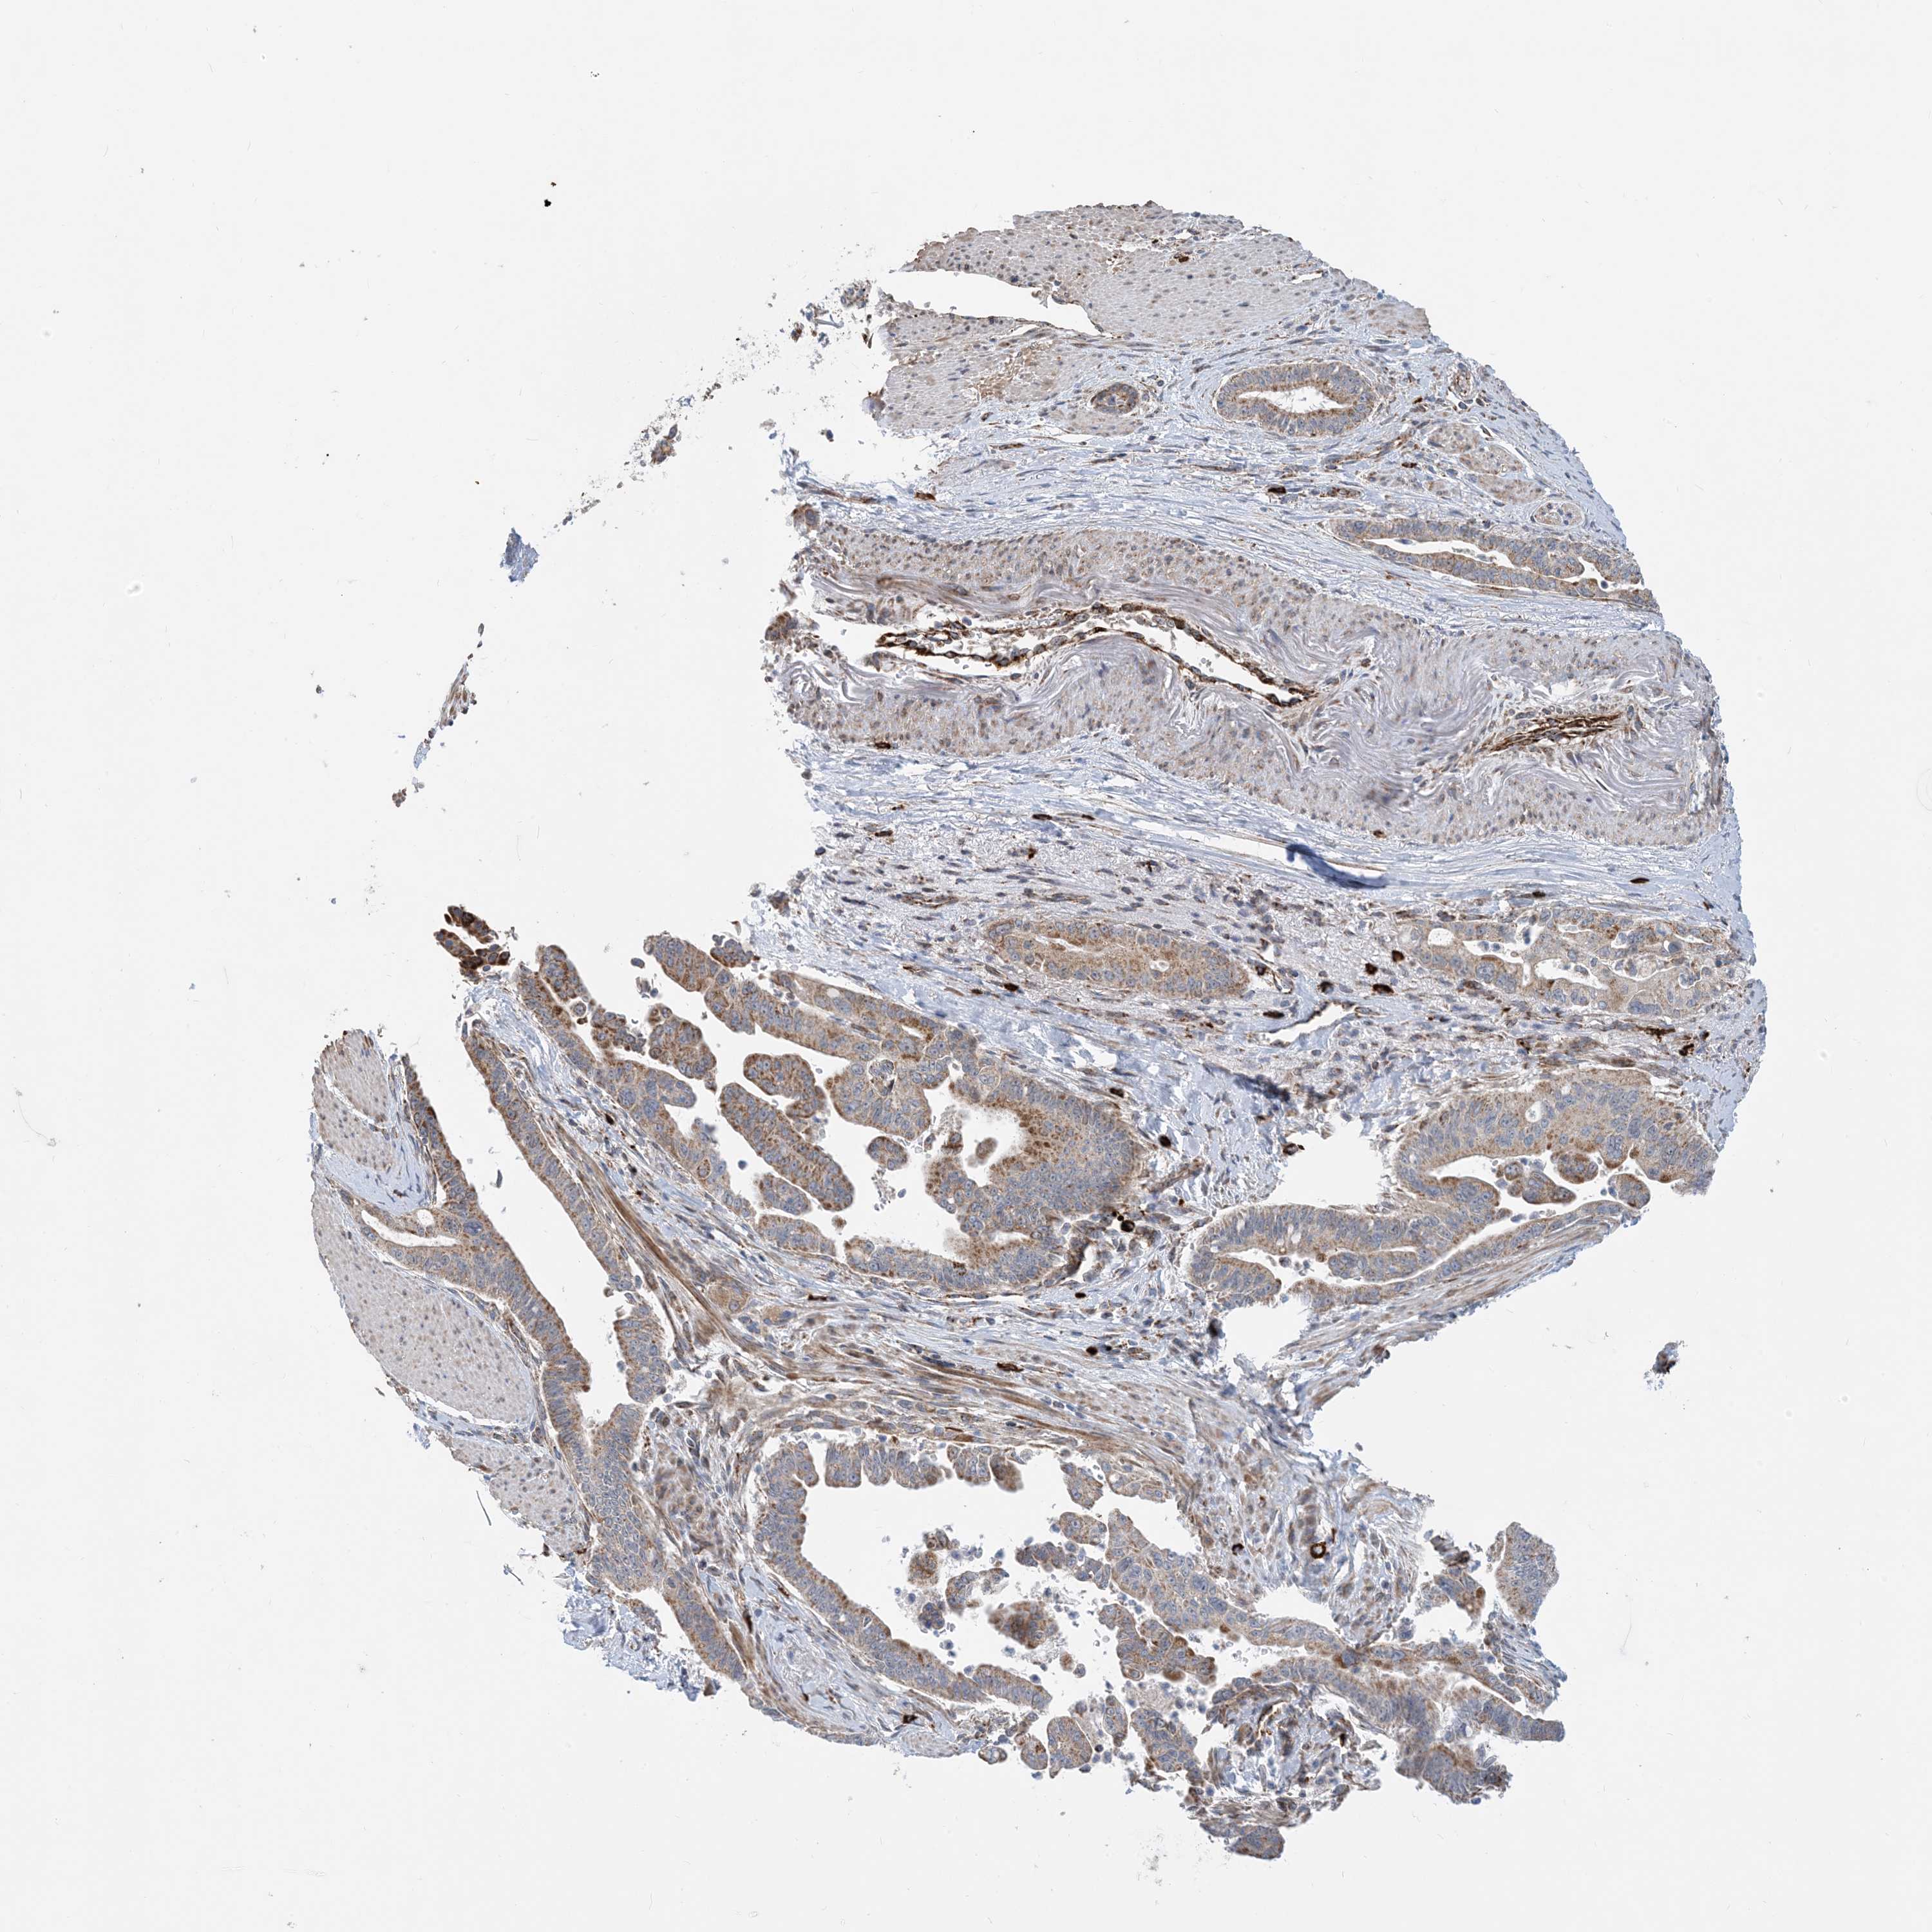

PANCREATIC CANCER - Protein expressioni

A mouse-over function shows sample information and annotation data. Click on an image to view it in a full screen mode. Samples can be filtered based on level of antibody staining by selecting one or several of the following categories: high, medium, low and not detected. The assay and annotation is described here.

Note that samples used for immunohistochemistry by the Human Protein Atlas do not correspond to samples in the TCGA dataset.

Antibody stainingi

Antibody staining in the annotated cell types in the current human tissue is reported as not detected, low, medium, or high, based on conventional immunohistochemistry profiling in selected tissues. This score is based on the combination of the staining intensity and fraction of stained cells.

Each image is clickable and will lead to virtual microscopy that enables deeper exploration of all samples and also displays staining intensity scores, fraction scores and subcellular localization as well as patient and tissue information for each sample.

Antibody HPA008755

Antibody HPA036547

Staining

High

Medium

Low

Not detected

Intensity

Strong

Moderate

Weak

Negative

Quantity

>75%

75%-25%

<25%

None

Adenocarcinoma, metastatic, NOS